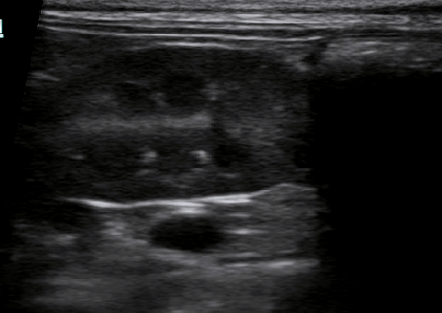

Односторонняя гипоплазия почки (рис 1), которая никак себя не проявляет, лечения не требует. Если функции пораженного органа сохранены хотя бы на 30%, то за животным ведется наблюдение, время от времени проводится обследование. При возникновении симптомов проводится симптоматическое лечение.

Рис.1. Гипоплазированная почка на он её здорово симметричной почки.